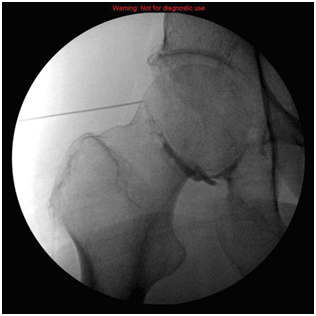

The areas around the hip joint that can be injected are many but the common areas are trochanteric injection and iliopsoas tendon injection (Figure 1).

Figure 1 Extra articular hip injection.